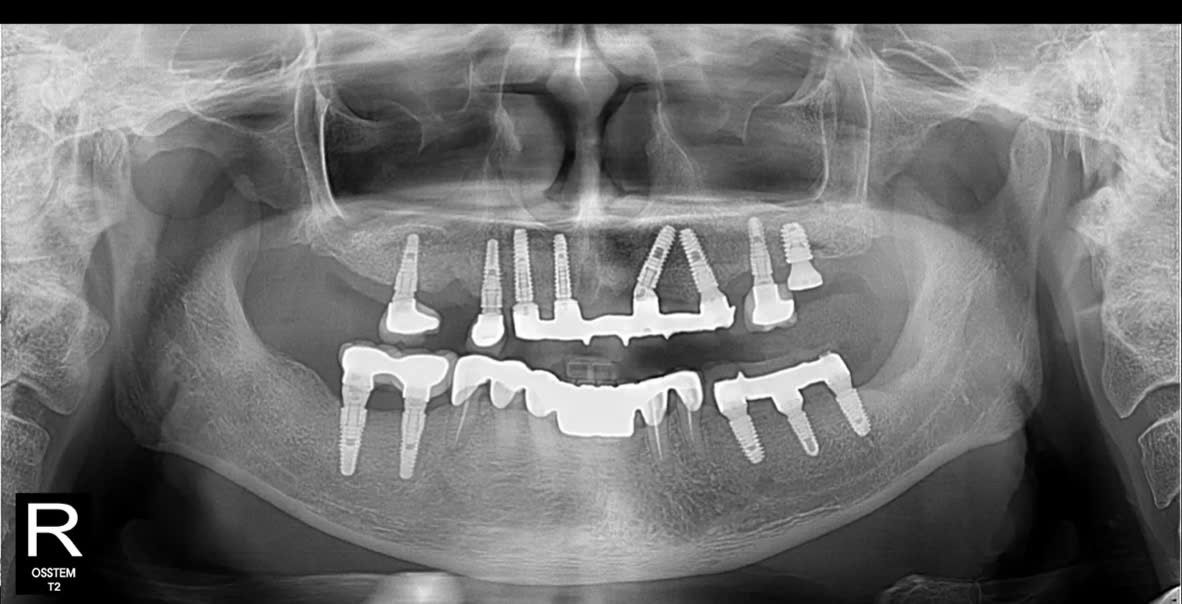

Khi tiếp nhận thăm khám, bác sĩ nhận thấy:

- Hàm trên: chỉ còn lại vài trụ Implant cũ đã được đặt cách đây hơn 10 năm, hiện nay có dấu hiệu tiêu xương quanh trụ, không còn đảm bảo chức năng nâng đỡ phục hình.

- Hàm dưới: nhiều mão sứ và cầu răng đã xuống cấp, lỏng, gãy, gây mất cân đối khớp cắn và ảnh hưởng đến khả năng ăn nhai.

- Xương hàm có dấu hiệu tiêu và mỏng, cần được đánh giá kỹ qua phim CT ConeBeam 3D để xác định có cần ghép xương, nâng xoang trước khi cắm trụ mới.

- Hàm trên: Cấy ghép Implant toàn hàm bằng kỹ thuật All-on-5 – giải pháp phục hồi tối ưu giúp tái tạo toàn bộ hàm răng trên chỉ với 5 trụ Implant, mang lại độ vững chắc và thẩm mỹ cao.

- Hàm dưới: Đặt thêm Implant Hiossen (Mỹ) để phục hình lại các răng mất, đảm bảo khả năng chịu lực tốt, tích hợp xương nhanh và tuổi thọ lâu dài.